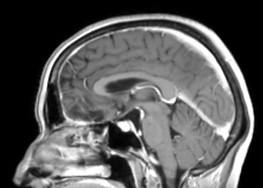

Chiari I malformācija

Pirmsoperācijas attēls. Redzama smadzenīšu noslīdēšana un saspiešanās ar muguras smadzenēm. Smadzeņu škidruma plūsma ir apgrūtināta.

Pēcoperācijas attēls. Redzama brīva telpa ap smadzenītēm, saspieduma vairāk nav. Smadzeņu škidruma plūsma ir netraucēta.